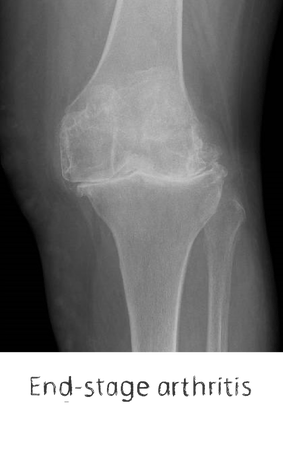

Plain film x-rays are taken to assess the joint

These are usually taken prior to your appointment. These help to confirm the diagnosis, assess the wear pattern and look for particular deformities. They can show old metalware and its position in the bone.